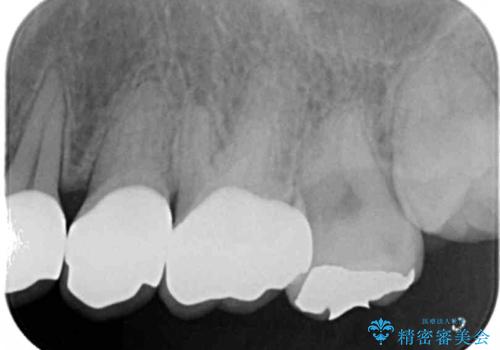

- K-POP(Kポップ)アイドルのような歯にしたいと希望され来院された患者様です。

矯正を途中でやめてしまったとのことで、歯に矯正の接着材が残っており着色も顕著でした。

奥歯の咬合面にはレジンが盛られた状態でした。

見た目と咬み合わせを改善するため、セラミッククラウンによる治療を行いました。